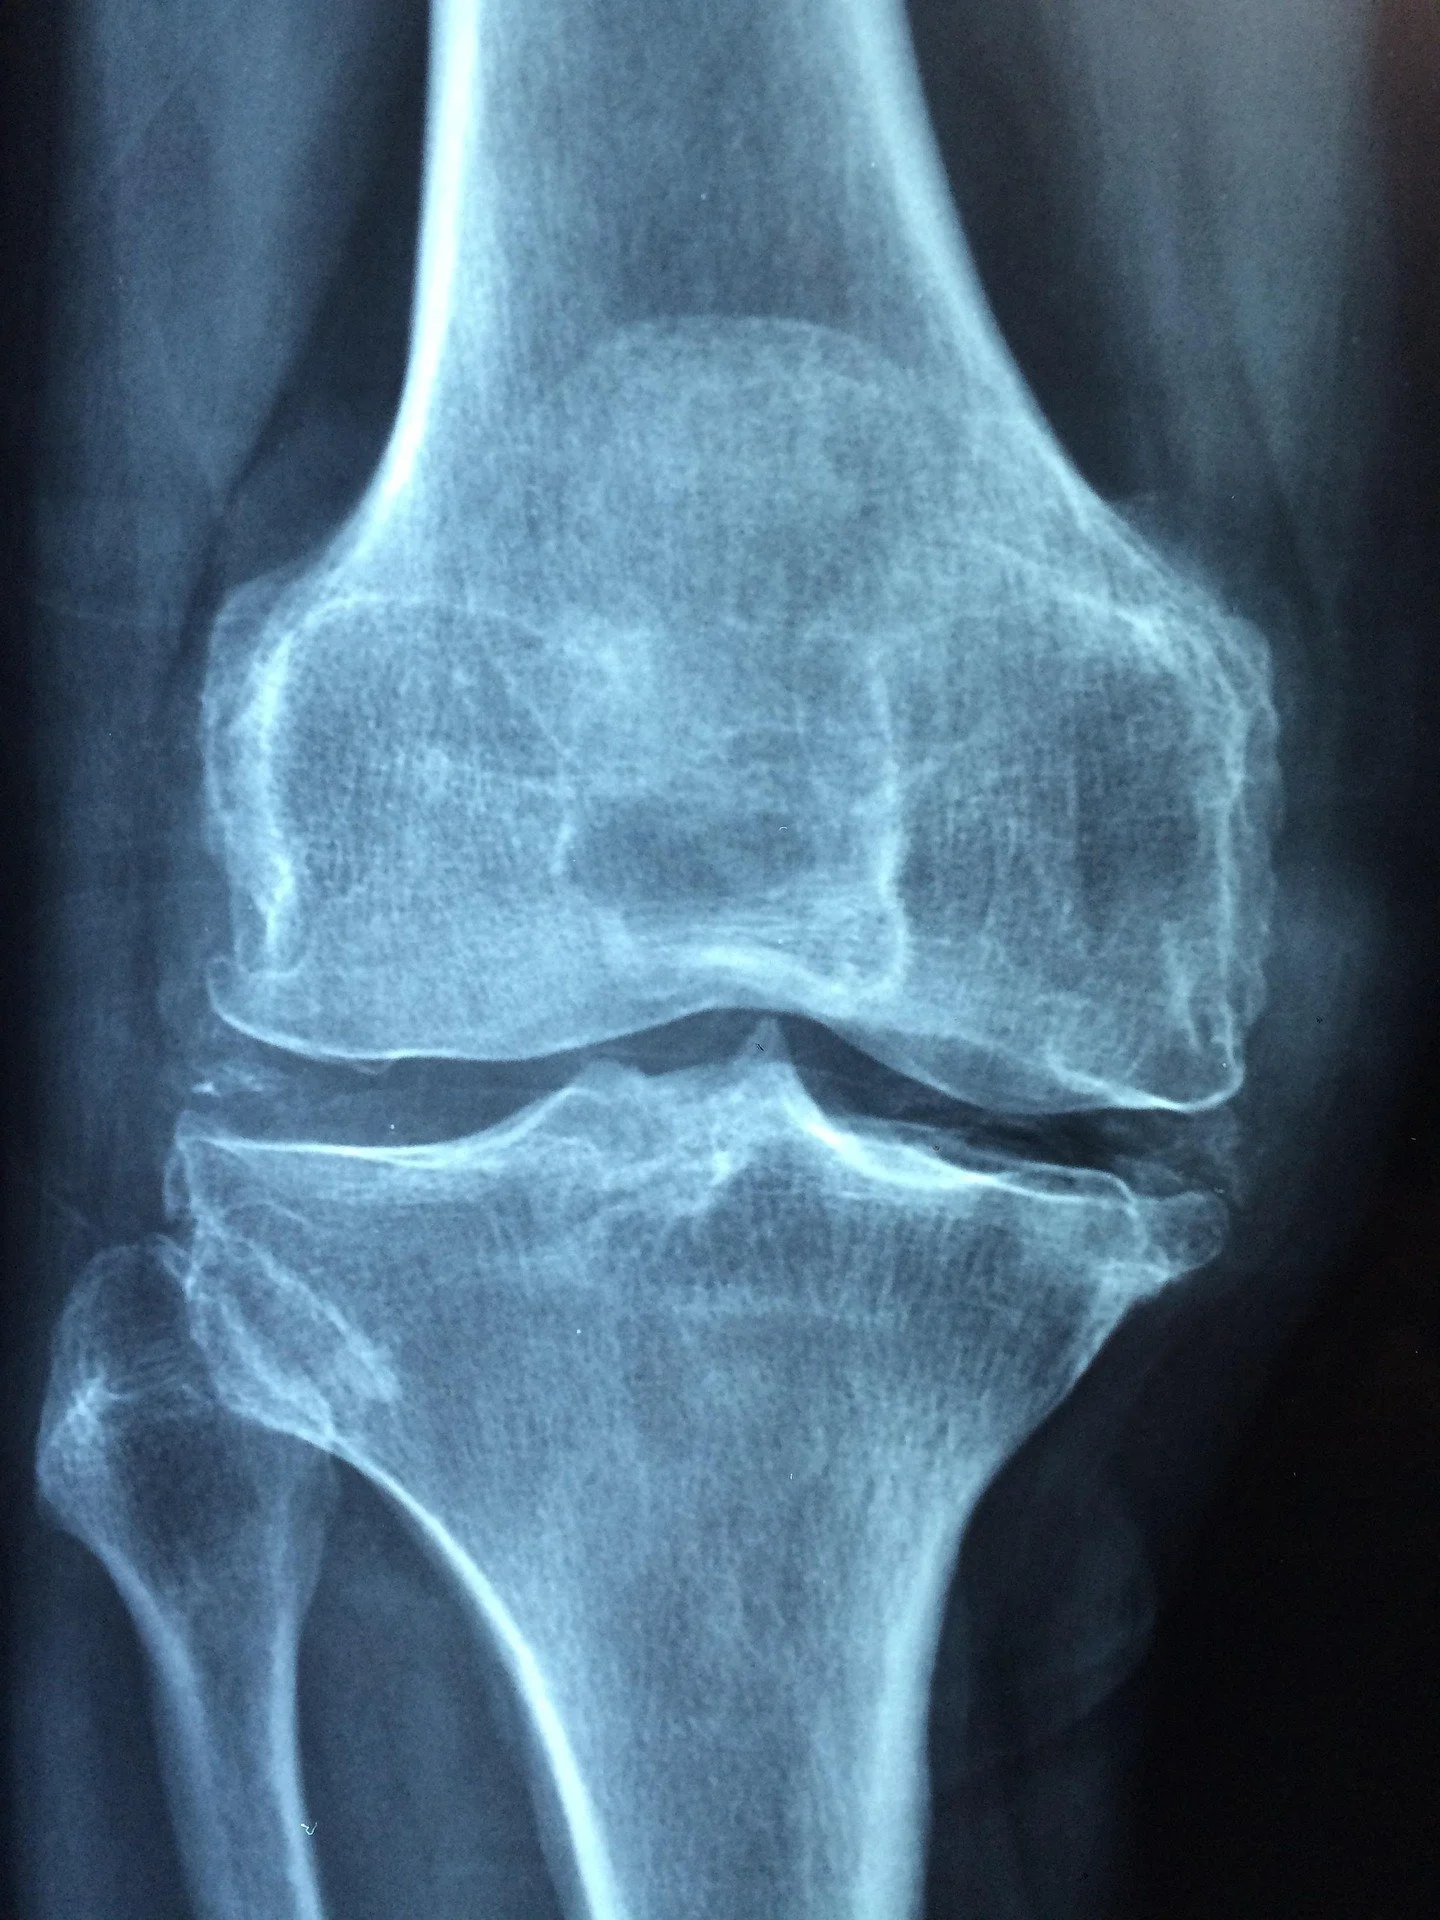

Tako i u tu grupaciju bolesti spadaju artritis i artroza (ili osteoartritis). Artritis je opći pojam za upalu zglobova, dok je artroza najčešći tip koji predstavlja degenerativnu bolest uzrokovanu trošenjem i propadanjem hrskavice, što dovodi do boli, ukočenosti i smanjene pokretljivosti zglobova. Dok artritis označava upalu zglobova (npr reumatoidni artritis) koja ima najčešće autoimuni karakter, artroza se prvenstveno odnosi na degeneraciju (trošenje) hrskavice, s tim da se ti procesi često preklapaju, degeneracija može izazvati upalu, a upala pogoršati degeneraciju. Postepeno progresivno propadanja zglobova rezultira smanjenom pokretljivosti, propisivanjem velikih količina analgetika, te najčešće završava pozamašnim profitom ortopeda i proizvođača umjetnih dijelova tijela (npr koljena, kukova, kralježnica).

Artroza koja predstavlja trošenje hrskavice česta je u starijih ljudi, pretilih osoba ili kod osoba koje rade poslove koji uključuju „trošenje“ određenih zglobova. Simptome ove bolesti uključuje bol, jutarnja ukočenost, škripanje/pucketanje, oticanje ili deformacija zglobova. Najčešće zahvaća koljena, kukove, kralježnicu i stopala. Artritis, tj upala zglobova, spada u grupaciju autoimunih bolest ili može biti uzrokovan gihtom (odlaganjem urične kiseline u zglobovima). Simptomi ovog stanja uključuju bol, ticanje, toplinu i crvenilo te ukočenost zglobova, osobito ujutro ili nakon mirovanja, uz moguću simetričnu zahvaćenost zglobova (npr obje šake), umor, slabost, groznicu. Artritis i artroza tretiraju se konvencionalnim zastarjelim metodama, koje nikome nisu izliječile bolest. Smatra se da je uzrok bolesti nepoznata autoimunost ili starenje. Priče da postoje neizlječive bolesti nisu više prigodne u današnjem dobu. Uzroci svih bolesti su poznati i transparentni u znanstvenim studijama, no medicinski lobiji nisu spremni liječiti bolesti. Izliječen pacijent je izgubljena mušterija.

Hrskavica zglobova je specifično vezivno tkivo s čvrstom međustaničnom tvari i hrskavičnim stanicama (hondrocitima) koji pružaju potporu, amortizaciju i lakše kliženje zglobova. Hrskavica je građena većinom od vode i kolagena (tip II) koji daje čvrstoću, a zajedno su umreženi s hondrocitima i proteoglikanima. Pošto kolagen stvaraju hondrociti u zglobovima, postavlja se pitanje; zašto u nekim slučajevima hondrociti smanjeno stvaraju kolagen ili ga u određenoj životnoj dobi prestanu stvarati? Odgovor leži u manjku nutrijenata potrebnih za stvaranje kolagena u zglobovima. Da bi prevenirali nedostatke kolagena u hrskavici, potrebno je imati i dovoljnu količinu gradivnih elemenata kolagena. Prvenstveno tu su bitni vitamin C, sumpor, bakar i cink. Također od mikroelemenata najbitniji je mineral koji se naziva mangan, a odgovoran je za izgradnju proteoglikana i kolagena u zglobovima. Uporaba namirnica koje su tretirane herbicidom koji se zove glifosat drastično smanjuje bioraspoloživost mangana u tijelu, stoga je potrebno obratiti pažnju i na podrijetlo namirnica koje se konzumiraju, odnosno koje su se konzumirale kroz cijeli život. Posebnu važnost čvrstoći cijelog zgloba daje propisno ugrađen kalcij (s pomoću vitamina K2), fosfor, te mineral bor. Svi spomenuti nutritivni elementi promoviraju obnovu tkiva, daju čvrstoću kostima, djeluju antioksidativno te sprečavaju upalu u zglobovima, čim se štiti hrskavicu. Manjak navedenih vitamina i minerala nastaje zbog smanjenog unosa putem hrane, tj. loše prehrane, smanjene apsorpcije hranjivih tvari zbog problema u radu probavnog sustava, ili zbog pretjeranog utroška tih nutrijenata u nekim drugim procesima u tijelu (na uštrb funkcije zglobova). U većini namirnica koje konzumiramo, uključujući voće i povrće, zbog industrijskog i ekstenzivnog načina uzgoja, te manjka minerala i hranjiva u tlu, konzumiramo plodove bez esencijalnih nutrijenata. U starosti, manjak unosa vitamina i minerala putem hrane kroz cijeli životni vijek ima kumulativni učinak, te tijelo počinje razgrađivati vlastito vezivno tkivo (hrskavicu) kako bi moglo doprijeti do nutrijenata koji imaju ozbiljne uloge u metaboličkim procesima lociranim negdje drugdje u tijelu (npr. mozak ili jetra).